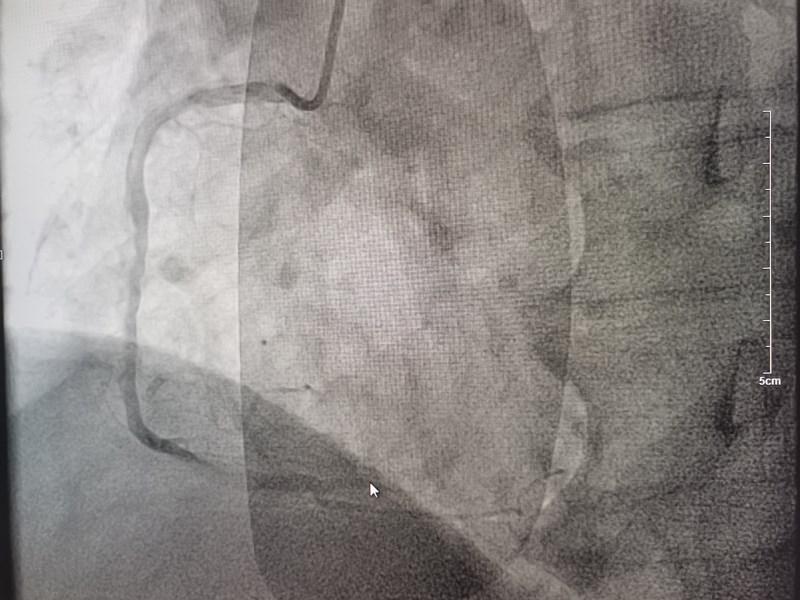

時間就是心肌,時間就是生命!一場生命的接力就此展開!心內(nèi)科團隊立即啟動胸痛綠色通道,電話通知導管室安排手術人員到位。董學濱副主任、汪韶君副主任醫(yī)師,以及導管室工作人員有條不紊地備好主動脈球囊反搏機、呼吸機等急診冠脈造影術前的各項準備工作,以及術中可能出現(xiàn)的各種突發(fā)狀況的應急預案。23:42分,造影手術正式開始,術中顯示裴某巨大的右冠狀動脈全程彌漫性病變,PLA近端完全閉塞。此時裴某生命體征極不穩(wěn)定,表情淡漠血壓低,隨時可能出現(xiàn)心臟驟停!治療承受著巨大的壓力和風險,心內(nèi)科團隊迎難而上,迅速將導絲通過閉塞血管,球囊擴張、打通閉塞的血管、植入支架,整個手術過程嫻熟、精準。隨著阻塞血管血流的恢復,裴某慢慢睜開了眼睛,神志恢復,胸痛癥狀消失,生命體征逐漸趨于平穩(wěn)。整個手術僅用時一小時。

術前